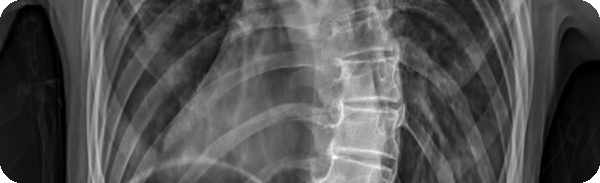

健升AI Cobb角智能研判大模型

脊柱侧弯影像分析Cobb角快速识别方案

健升AI Cobb角智能研判系统可与影像科无缝对接,实现X光片Cobb角的自动识别、结构化输出与系统级API集成,帮助医务人员快速完成脊柱侧弯影像评估,显著提升效率与准确性。